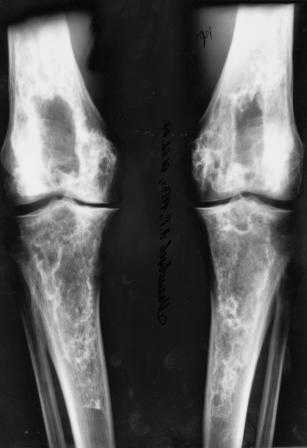

Представленные Вами данные о пациенте 57 дет с болезнью Альбертс-Шенберга чрезвычайно интересны, но диагноз вызывает большие сомнения. Для мраморной болезни характерно прееобладание склероза, а на представленных рентгенограммах преобладает симметричная дезорганизация архитектоники губчатой кости в эпиметафизарной зоне дистальных отделов бедер и голеней.

Мне кажется, представленные рентгенограммы скорее соответствуют варианту фиброзной дисплазии который был описан М. Campanacci (1976) или

обызвествляющей фиброме H.E.Schlitter (1958).

Уважаемый Константин Иванович! Полностью согласен с проф. Михайловым, данный случай не похож на мраморную болезнь, при которой имеется резкое, строго симметричное и генерализованное уплотнение костной ткани (остеопетроз), и кость оказывается построенной преимущественно из гомогенного компактного костного вещества. Для примера привожу случай из архива нашего института (бедренные, плечевые кости и таз, рис 1,2,3)

Изменения структуры костей у Вашего пациента больше похожи на полиоссальную форму фиброзной дисплазии или болезнь Педжета, возможены также инфаркты костного мозга б.берцовых костей. К сожалению, качество снимка не очень хорошее, непонятно, сохранен ли кортикальный слой б.берцовых костей по передней поверхности.